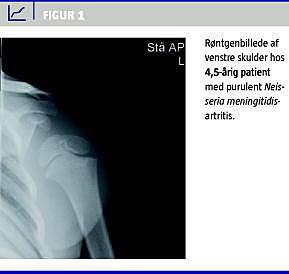

Efterfølgende blev patienten sat i bredspektret intravenøs antibiotisk behandling med cefuroxim (500 mg × 3). Den antibiotiske behandling blev skiftet til penicillin efter det overraskende dyrkningssvar: Neisseria meningitidis, der var følsom for penicillin. På det primære røntgenbillede var der en ansamling, ellers var der normale røntgenbilleder i forløbet (Figur 1 ).